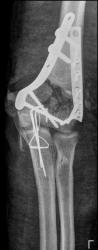

На представленных раннее снимках был внутрисуставной многооскольчатый перелом дистального эпифиза плечевой кости, со смещением отломков по ширине и с некоторым их захождением, так же многооскольчатый перелом локтевого отростка. Однако сегодня сделали рентген-контроль после открытой репозиции:

Думаю травматологи хорошо справились с этим делом, фиксация отломков дистального эпифиза плечевой кости дугообразными пластинами с шурупами  и фиксация отломков локтевого отроска 2мя спицами. Правда исход минимум посттравматический остеоартроз, скорее всего не минуем.